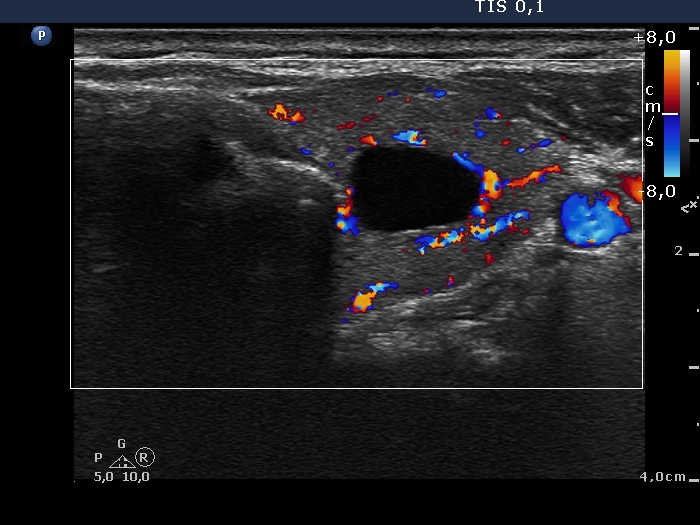

Consecutively operated patients with autoimmune thyroid disease - case 19 (1771) (ultrasonographic picture 7)

Upper part of the left lobe, transverse scan, color Doppler mode. The vascularization is increased within the lobe.